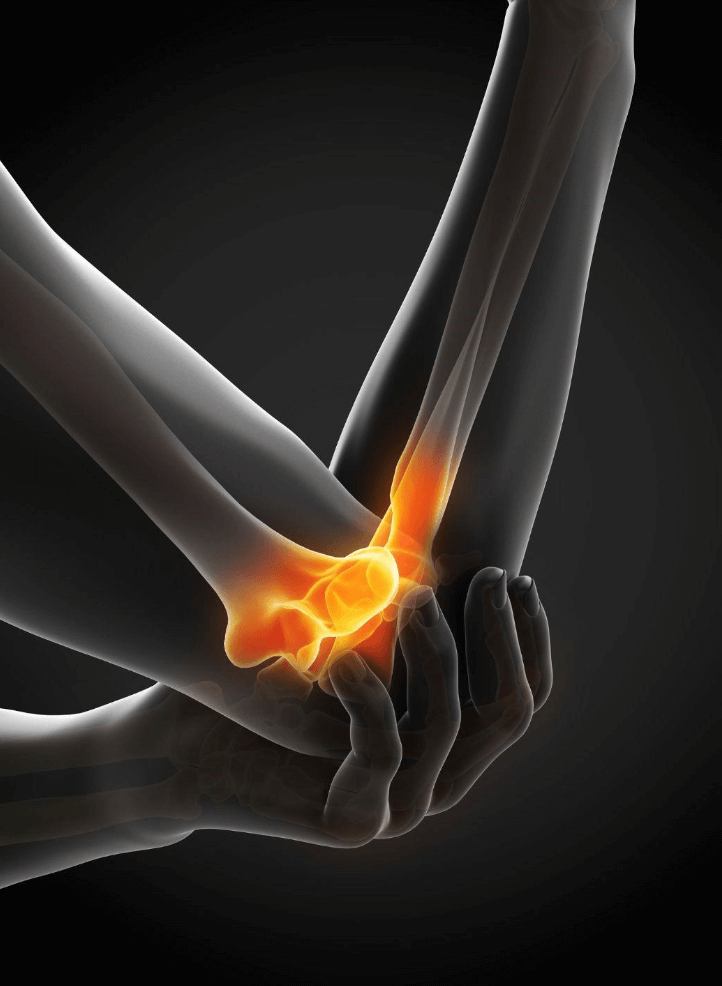

What Is Arthritis? Arthritis refers to inflammation of the joints. It’s not a single condition but a broad term thatcovers over 100 different types. The most common include: The main symptoms of arthritis include: If left untreated, arthritis can significantly impact your mobility and independence. This is where physiotherapy plays a crucial role. How Physiotherapy […]